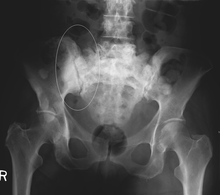

Bone is the third most common location for metastasis, after the lung and liver.[5] While any type of cancer is capable of forming metastatic tumors within bone, the microenvironment of the marrow tends to favor particular types of cancer, including prostate, breast, and lung cancers.[3] Particularly in prostate cancer, bone metastases tend to be the only site of metastasis.[2] The most common sites of bone metastases are the spine, pelvis, ribs, skull, and proximal femur.[6]